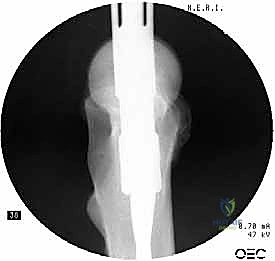

باستخدام جهاز الأشعة السينية المرئية المستمرة (C-Arm Fluoroscopy) داخل غرفة العمليات، يقوم الدكتور هطيف بإعادة العظام المكسورة إلى محاذاتها التشريحية الصحيحة عن طريق الشد والتدوير الخارجي للساق، وكل ذلك يتم مراقبته على الشاشة بدقة متناهية.

4. توسيع القناة وإدخال المسمار

يتم استخدام أدوات حفر خاصة (Reamers) لتوسيع القناة النخاعية بلطف لتستوعب المسمار المصنوع من التيتانيوم. بعد ذلك، يتم انزلاق المسمار النخاعي الرئيسي داخل العظم حتى يصل إلى العمق المطلوب.

6. التثبيت السفلي (Distal Locking)

لضمان عدم دوران العظمة حول المسمار، يتم إدخال مسمار أو مسمارين صغيرين في الجزء السفلي من المسمار النخاعي عبر شقوق جلدية دقيقة جداً (لا تتجاوز 1 سم).